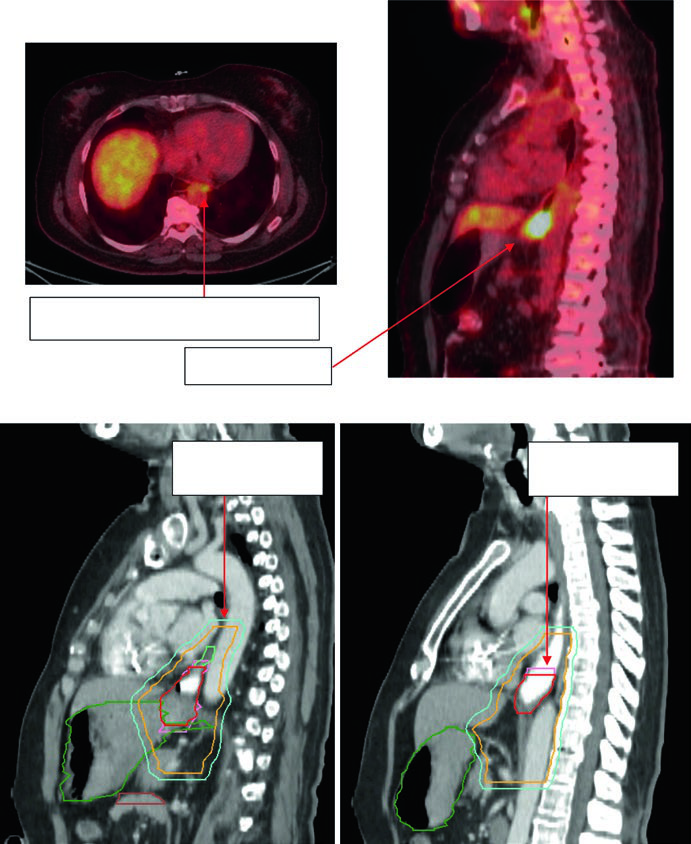

Caso 2: Adenocarcinoma Torácico Inferior — 81 anos, uT3N1

Paciente de 81 anos com adenocarcinoma esofágico torácico inferior uT3N1. O PET demonstrou captação no primário e no linfonodo paratraqueal nível 4R. A endoscopia revelou adenocarcinoma circunferencial parcialmente obstrutivo entre 31 e 35 cm dos incisivos. O EUS confirmou doença T3 com linfonodo nível 4R suspeito. Os contornos aplicaram margem de 0,5 cm de GTV para CTV no linfonodo 4R e cobertura inferior de 3–4 cm. Volumes: plexo braquial (roxo), estômago (verde escuro), GTV esofágico (vermelho), ITV (rosa), GTV nodal (verde claro), CTV (laranja), PTV 50,4 Gy (azul escuro).

Caso 3: Adenocarcinoma de JGE — 75 anos, uT3N0

Paciente de 75 anos com adenocarcinoma de junção gastroesofágica uT3N0. Os contornos demonstram extensão do CTV para o estômago proximal, com cobertura até o eixo celíaco. Volumes delineados: estômago (verde escuro), intestino grosso (marrom), GTV esofágico (vermelho), CTV (laranja), PTV 50,4 Gy (ciano). A inclusão do eixo celíaco é mandatória para tumores distais e de JGE.

Caso 4: Adenocarcinoma de JGE — 59 anos, uT3N2

Paciente de 59 anos com adenocarcinoma de JGE uT3N2. O PET demonstrou linfonodos paraesofágicos captantes e tumor primário localizado entre 36 e 40 cm dos incisivos. O corte sagital da TC de planejamento mostra o ITV refletindo o movimento do GTV, com CTV cobrindo 3–4 cm acima do ITV. Volumes: estômago/duodeno (verde escuro), GTV nodal (verde claro), GTV esofágico (vermelho), ITV (rosa), CTV (laranja), PTV 50,4 Gy (ciano). Os linfonodos paraesofágicos foram incluídos no campo de tratamento.